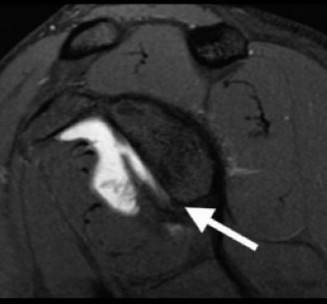

Which of the following findings is indicative of a subscapularis tendon tear?

The answer is (B). As the four layers of the lateral rotator interval insert onto the lesser tuberosity of the humerus, they form the “reflection pulley” that forms a sling around the tendon of the long head of the biceps before it enters the bicipital (intertubercular) groove. A tear of the upper part of the subscapularis can disrupt this reflection pulley and destabilize the biceps tendon, allowing it to sublux or even

dislocate out of its groove, usually in a medial direction. If this happens, the intertubercular groove will be empty on MRI. Often, a “pulley sign” will also be seen on MRI when this occurs. This is when contrast material extravasates extra-articularly just over the superior border of the subscapularis tendon on axial images (see Fig. 2–11).

Figure 2–11_Axial T1 MRI. Left: an empty intertubercular sulcus, positive pulley sign (straight _black arrow on left), and dislocated biceps tendon (curved black arrow). Right: fraying subscapularis tendon (arrow). (From Lyons RP, Green A. Subscapularis tendon tears. J Am Acad Orthop Surg. 2005;13(5):353–363.)